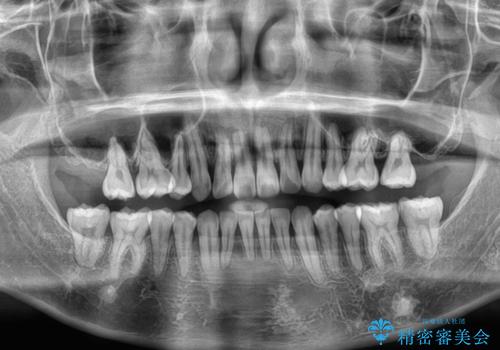

- 前歯のデコボコや八重歯を気にして来院された患者様です。

左右ともに奥歯の咬み合わせに問題があり、上顎臼歯が前方位にある状態で、結果として上顎前歯全体が前方位かつ叢生になっていました。

また、左右ともに上顎最後臼歯が頬側に転移していたため、補助装置を用いて舌側に移動をさせながら、上顎前歯を引っ込むように移動させることとしました。

口元の突出感を解消させるため上顎左右第一小臼歯2本を抜歯して、ワイヤー装置にて矯正治療を行うこととしました。

上顎のみの抜歯矯正であったため、治療期間が長期化することが予想されましたが、何とか3年弱の期間で想定通りの仕上がりで終えることができました。